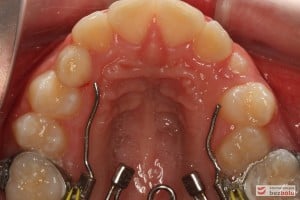

Rodzice zgłosili się z pacjentem celem rutynowej kontroli ortodontycznej. Wykonano OPG i po analizie modeli diagnostycznych stwierdzono brak miejsca dla wyrzynania dolnej prawej piątki stałej oraz zwężenie szczęki wraz z rotacją górnych zębów szóstych. W łuku górnym w pierwszym etapie leczenia zastosowano Rotator, celem odrotowania 6-tek stałych oraz ekspansji łuku w wymiarze poprzecznym. Następnie zamontowano aparat stały metalowy do uszeregowania zębów w łuku. W łuku dolnym miejsce odtwarzano stosując aparat stały i odpowiednią mechanikę leczenia. Leczenie aktywne trwało 3,5 roku, po czym zastosowano terapię retencyjną (retainer stały w żuchwie oraz Płytkę Hawley’a w szczęce).